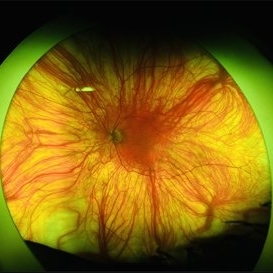

Foveal Hypoplasia / Ocular Albinism

Foveal Hypoplasia / Ocular Albinism

Aug 29 2024 by César Adrián Gómez Valdivia, MD

Fundus photograph of a 64-year-old female patient with foveal hypoplasia, ocular albinism and pendular nystagmus. Findings were bilateral. Retinal and choroidal vasculature are exquisitely beautiful.

Photographer: @eyemissu2

Imaging device: California ICG OPTOS

Condition/keywords: foveal hypoplasia, ocular albinism